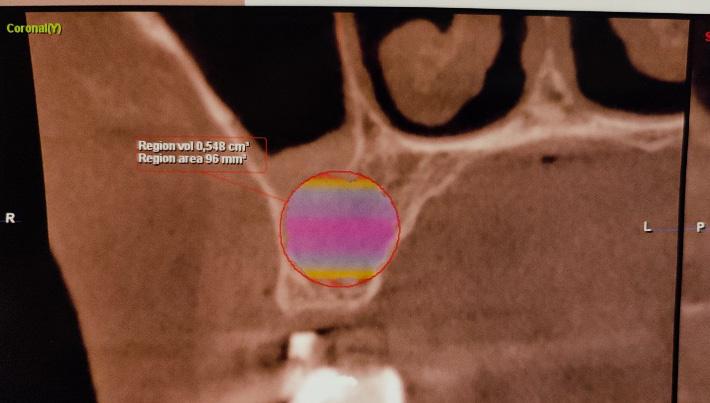

Aplicación de biomateriales post exeresis en un quiste inflamatorio radicular

Application of biomaterials post exeresis of a root inflammatory cyst

Javier Adrián Burgos, Renia Hurtado, Fabián Galindo, Juan Delgado....................................................97-106